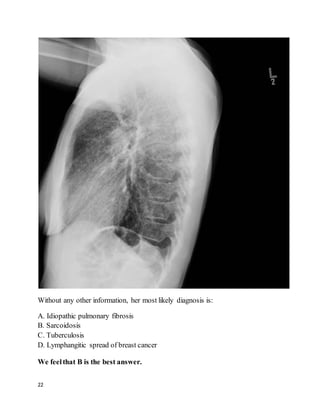

Without any other information, her most likely diagnosis is:

A. Idiopathic pulmonary fibrosis

B. Sarcoidosis

C. Tuberculosis

D. Lymphangitic spread of breast cancer

We feelthat B is the best answer.